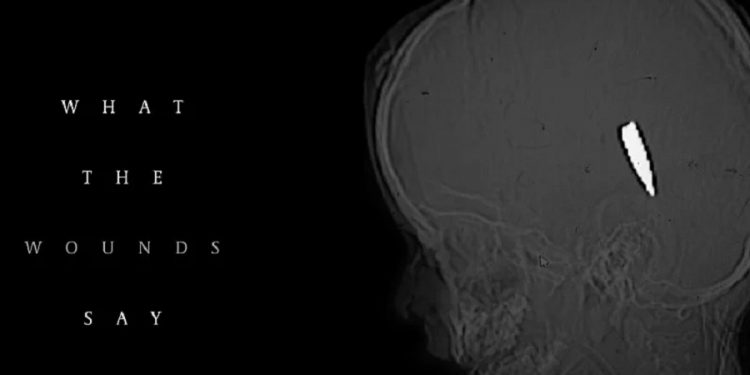

Petnaest njih reklo je da su liječili najmanje 114 djece u dobi od 15 godina ili mlađe s jednom ranom od vatrenog oružja u glavu ili prsa.

Većina te djece umrla je od zadobivenih rana. Slučajevi su dokumentirani između kraja 2023. i sredine 2025. u 10 različitih medicinskih ustanova.

Jedan od doktora, američki traumatolog Feroze Sidhwa, prisjetio se svog prvog dana u Evropskoj bolnici u Gazi u martu 2024. godine, gdje je pronašao četiri dječaka mlađa od 10 godina s identičnim ranama na glavi unutar 48 sati.

Tokom sljedećih 13 dana susreo se s još devetero djece sa sličnim ranama.

Intervjuirani doktori naglasili su da takve rane vjerovatno nisu slučajne. Forenzički stručnjaci koje su konzultirale novine rekli su da uzorak sugeriše ciljanu vatru, moguće snajperima ili dronovima.